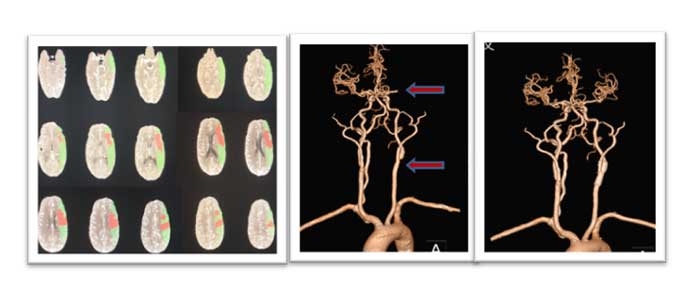

患者李某,男性,56岁,主因言语不利、右侧肢体无力、意识不清2小时20分就诊于我院急诊科,NIHSS评分26分。经我院静脉溶栓小组专家会诊,在征得家属同意后给予静脉溶栓,急诊行头颈部CTA(头颈部血管CT检查成像)及头颅CTP(头颅灌注成像)检查,提示:左侧颈总动脉远端及颈内动脉起始支架植入术后;左椎动脉重度狭窄,接近闭塞;左侧额叶、顶叶、颞叶、枕叶、小脑的血流灌注异常。患者病情危急,如不紧急处理,可能危及生命,后期还可能因大面积梗死需要行去骨瓣减压手术。为进一步挽救患者的低灌注组织,经神经外科介入小组专家会诊,征得家属同意后,在导管室为患者实施了急性血管内治疗,闭塞血管很快实现了再通,无需再行去骨瓣减压术。经抗血小板、强化降脂、改善循环、康复等治疗,患者一个月后复查影像时低灌注已消失,能够简单言语,右下肢可活动。

(左图)术前CTP显示:绿色区域左侧额叶、顶叶、颞叶、枕叶、小脑广泛血流灌注异常,其中红色为核心梗死。(中图)术前头颈部CTA显示:左侧大脑中近端闭塞及左侧颈内动脉起始重度狭窄,分别见红色箭头上、下。(右图)术后一个月左侧大脑中动脉闭塞已再通,颈内动脉起始狭窄支架置入术后恢复正常。